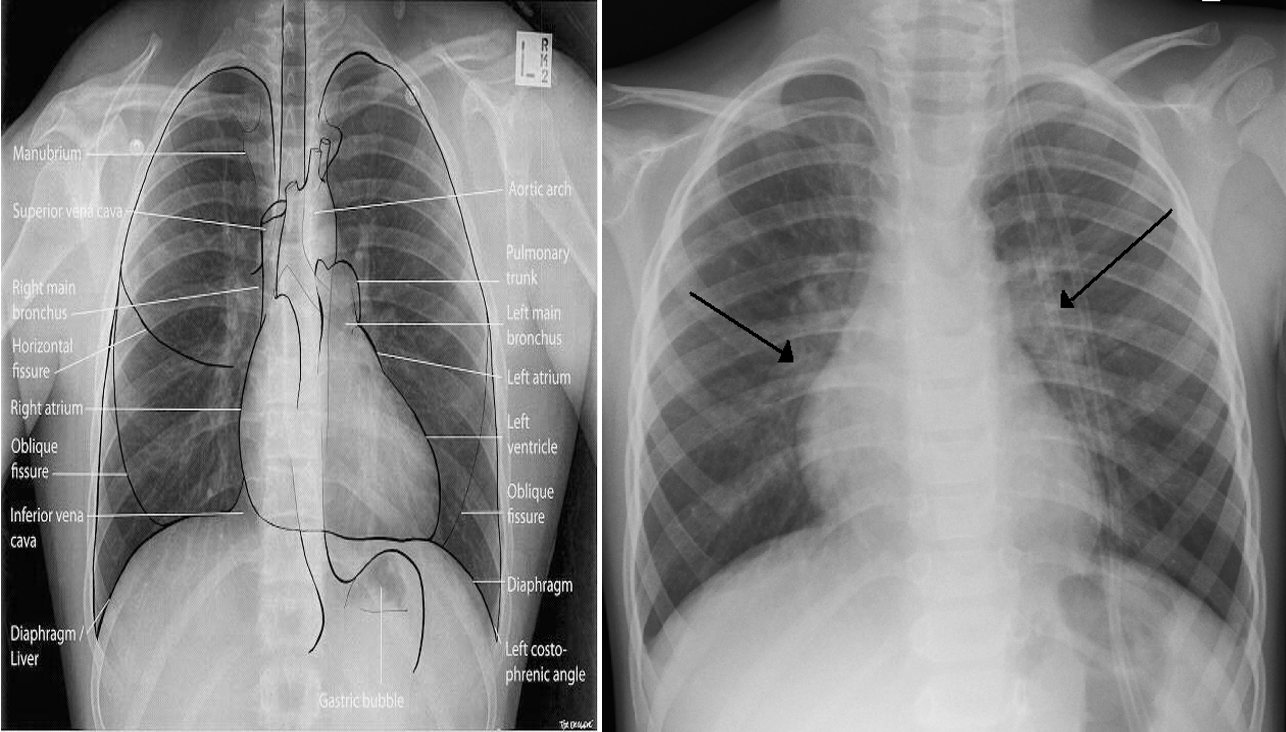

X-ray finding

• Hyperinflated lungs.

• In 30% scattered areas of opacity due to consolidation or atelectasis.

• An X-ray of a child with RSV showing the typical bilateral perihilar fullness of bronchiolitis.

Chest radiograph of a 3-month-old infant with severe RSV bronchiolitis: demonstrating a collapsed right upper lobe, hyperinflated left lung and bilateral perihilar, peribronchial thickening. The patient is intubated and has a nasogastric tube in situ.